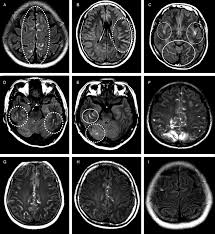

Patterns Of Blood Brain Barrier Bbb Breakdown In Patients With Download Scientific Diagram